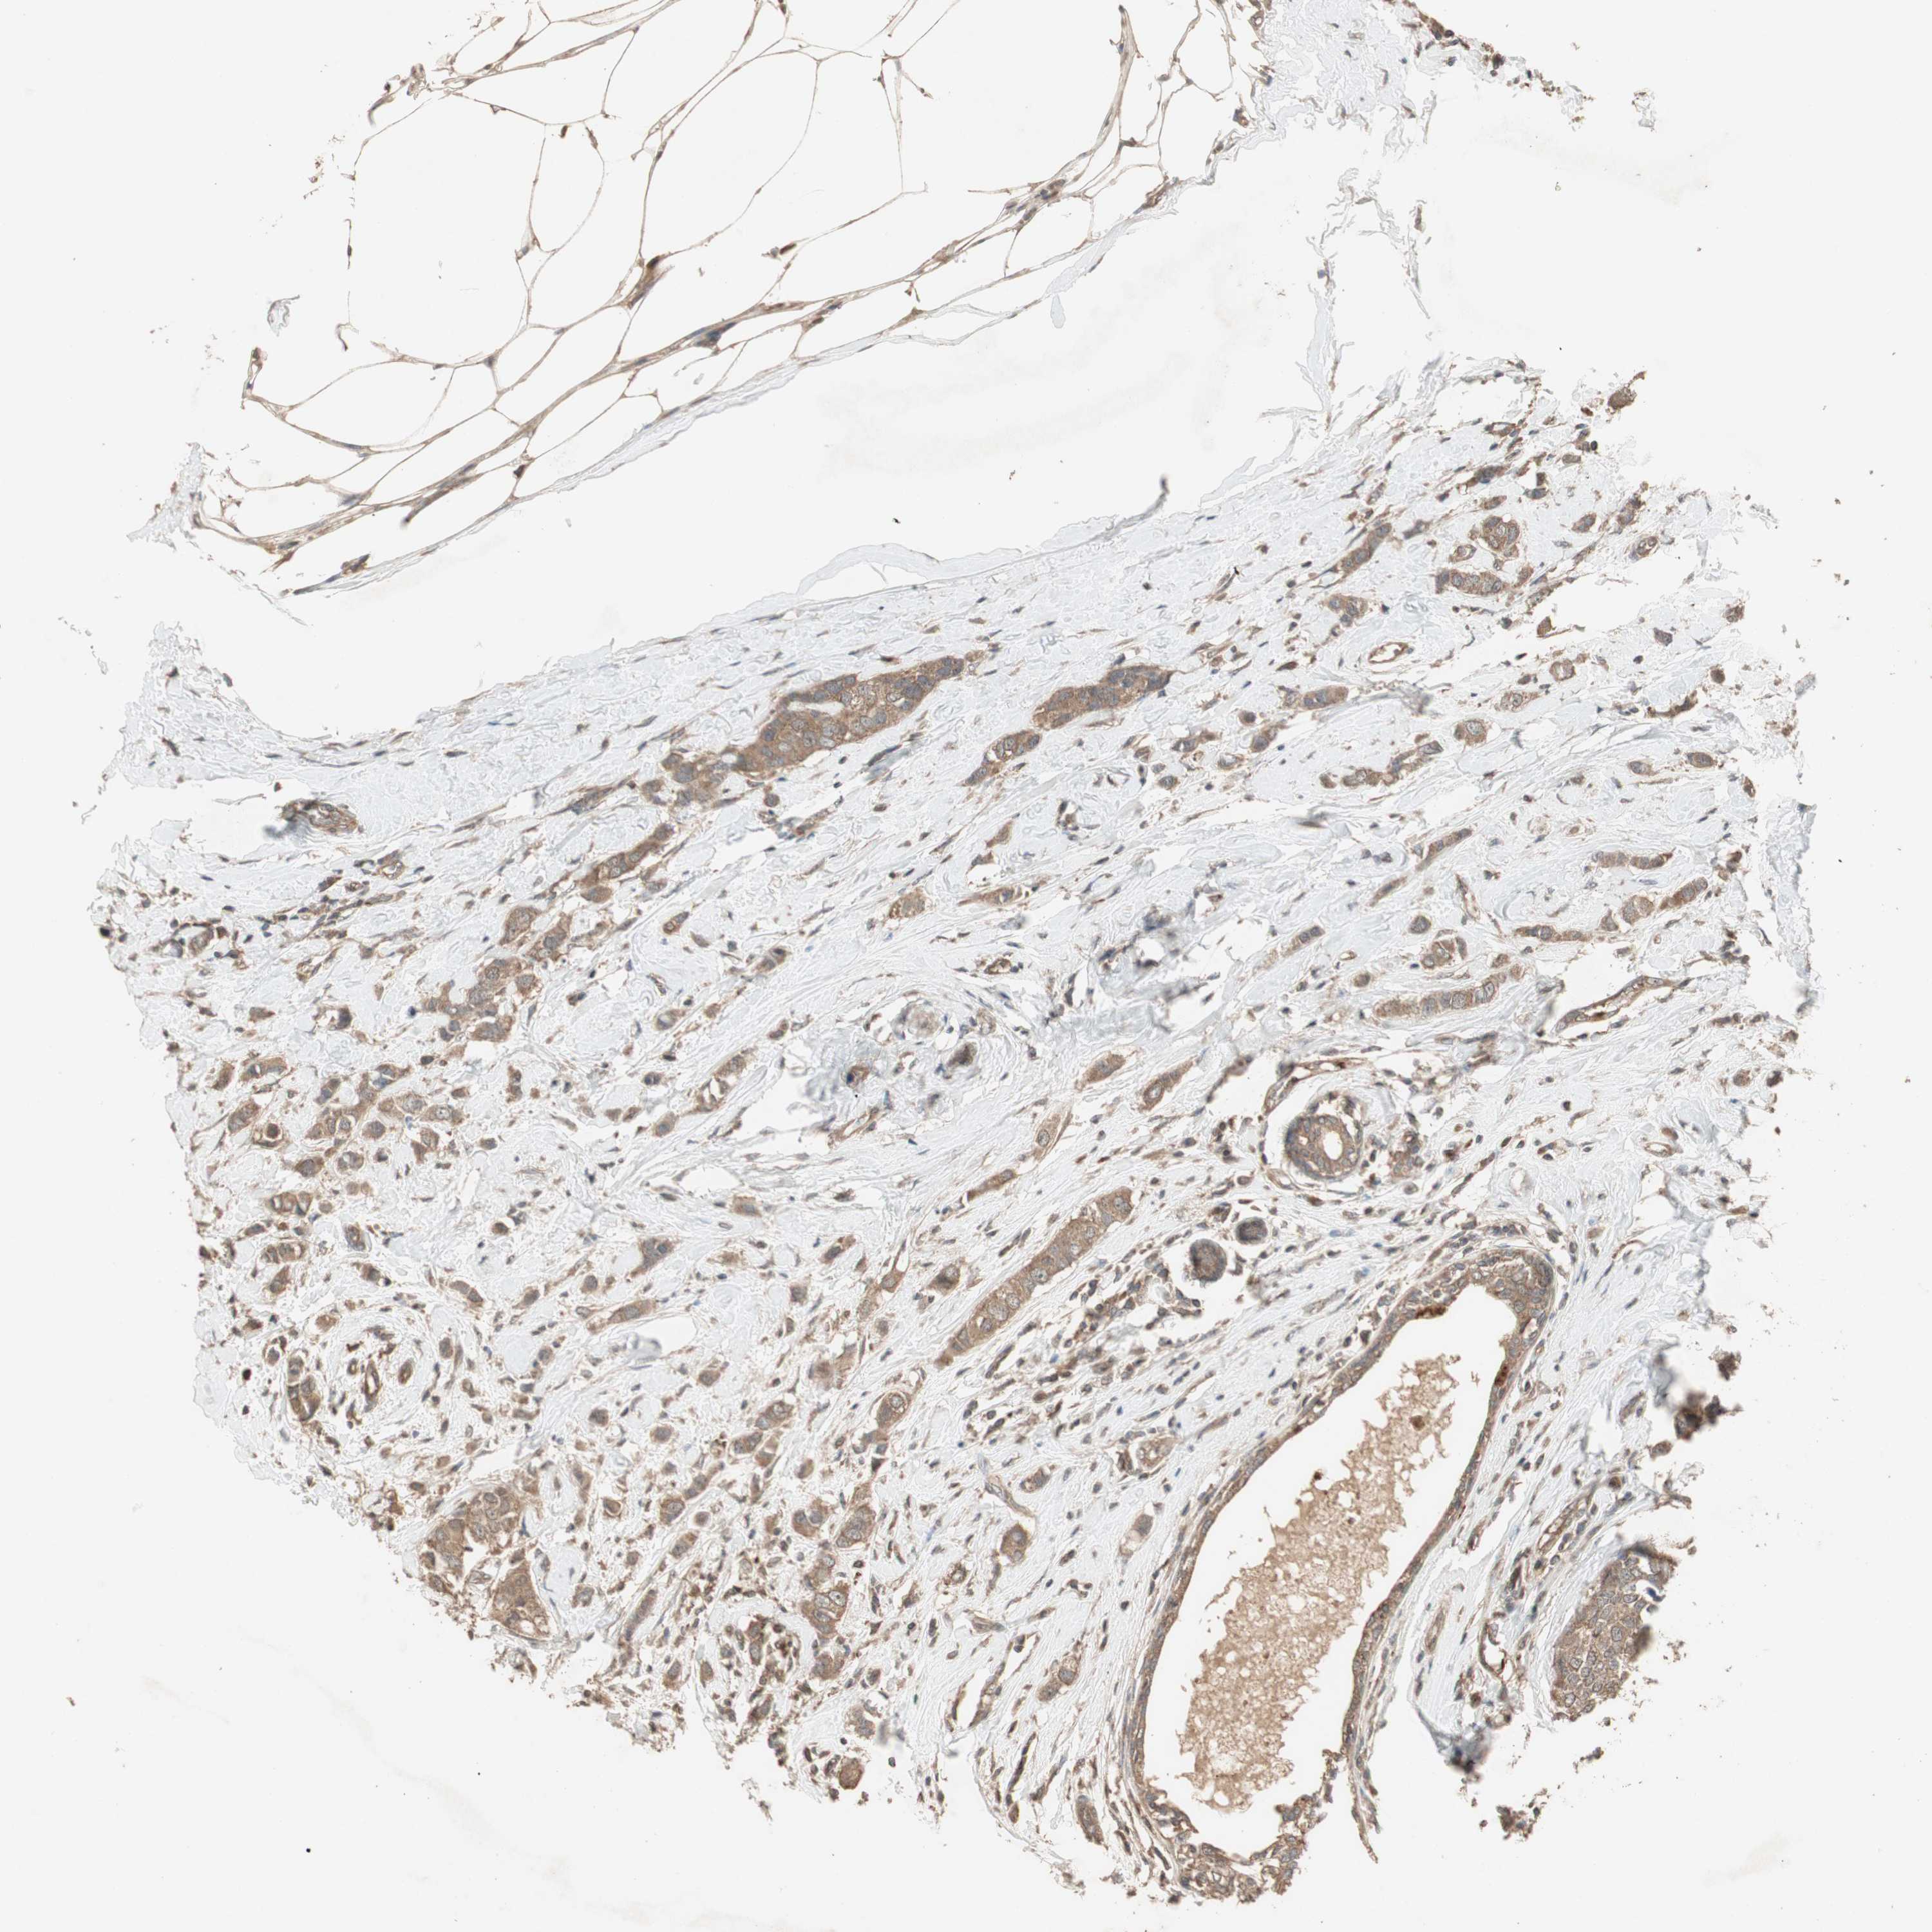

BRCA TCGA BRCA VALIDATION PROTEIN EXPRESSION